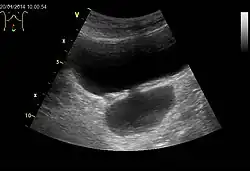

Die Harnblase ist bildgebend mittels Sonographie, Röntgen, Kernspintomographie, Computertomographie und endoskopisch darstellbar. Bildgebung der ersten Wahl sind die Verfahren ohne Röntgenstrahlung, zumeist die Sonographie.

Bei Hunden und Katzen lässt sich die Harnblase durch die Bauchwand ertasten, da sie bereits bei mäßiger Füllung vor dem Becken liegt.